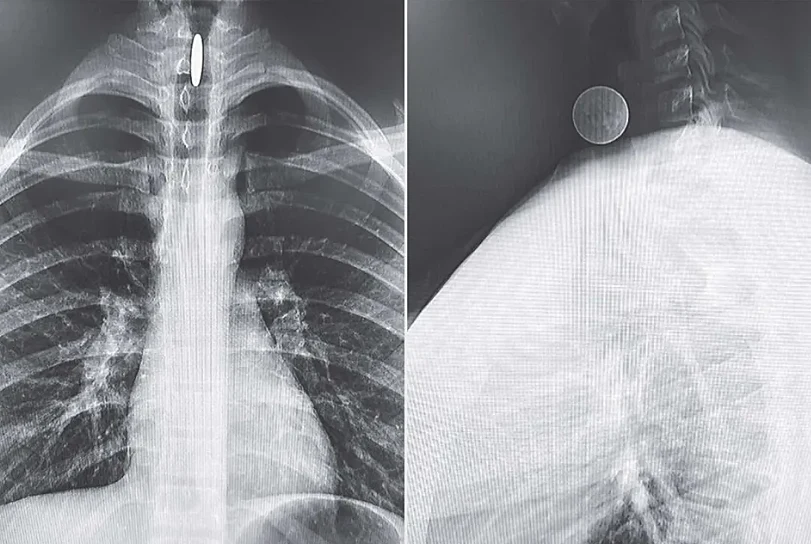

הרופאים ערכו צילומי רנטגן שחשפו כי המטבע נתקע בצורה אנכית בין מיתרי הקול לקנה הנשימה של הנער.

הצורה האנכית בה נתקע המטבע בגרונו של הנער למעשה הצילה אותו, משום שהיא אפשרה לאוויר לזרום ומנעה חניקה.